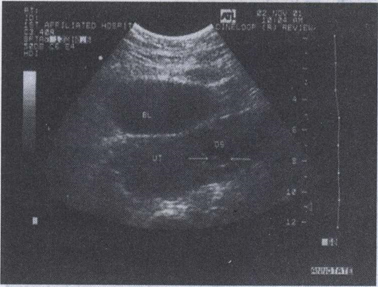

39.女,51岁,肛门停止排便排气1天。腹痛、无呕吐,有乙状结肠手术史。结合超声声像图,诊断为()

38.女,27岁,停经45天,阴道不规则出血1周余。尿妊娠试验阳性。结合超声图像,最可能的诊断为()